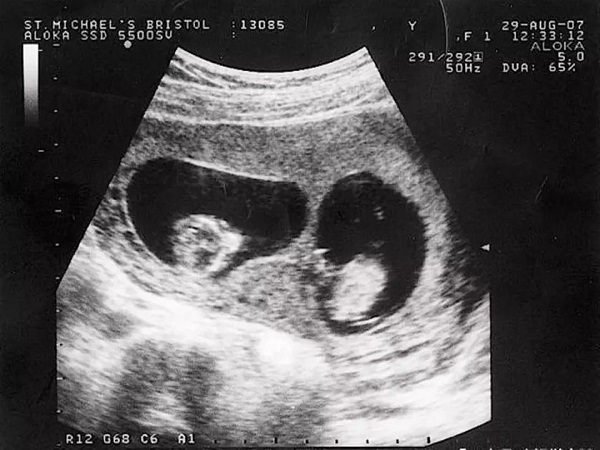

所谓的孕囊其实就是原始的胎盘组织,是被羊膜和血管网所包裹住的胚胎。孕囊是怀孕最初的形态,一般情况下胎儿还没有完成行程,但是这个时候已经会出现胎心和胎芽了,通过胎心的数量就能够判断出怀的是单胎还是双胎。如果出现两个胎心,那么就是双胎,可能是同性双胞胎,也有可能是龙凤胎,无论是哪种孕妇都需要及时到医院进行检查,确保胎儿的健康状况。

1两个胎心:在怀孕龙凤胎之后做B超检查就会看到有两个孕囊,出现两个胎心,出现这种情况就说明女性怀的是双胎,可能是龙凤胎,但是也可能是同性双胞胎;2妊娠反应大:女性在怀孕之后都是会出现一些早孕反应的,像恶心呕吐、食欲不振、嗜睡等,如果女性怀的是双胎龙凤胎的话,那么体内的激素就会更高,进而导致妊娠反应非常剧烈;3腹部明显:如果女性怀上龙凤胎那么就是两个孩子,女性的肚子也会比怀单胎的孕妇大一些,会导致女性的身体负担加重,需要注意休息。

如果怀孕之后B超显示两个孕囊一长一圆的话,有可能是龙凤胎,但是也有可能是同性双胞胎,因为孕囊的大小其实是会受胎儿的生长发育情况所影响的,所以出现一长一圆也是非常正常的,这并不能够确定胎儿的性别。所以建议大家不要太过相信一长一圆就是龙凤胎的说法。